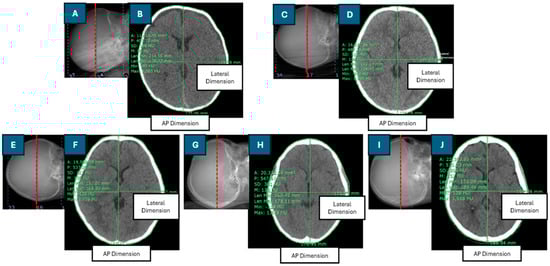

The Dw was calculated using the axial cross-sectional CT image of the brain, selected as the middle slice of the scan length. Patient dimensions and regions of interest (ROIs) were manually drawn using digital calipers and freehand ROI tools within the Synapse software version 4.3.2.1. An ROI was drawn around the perimeter of each patient’s head. The effective diameter (DEff) is the diameter of a circle with an area equivalent to the cross-sectional area of the patient [9]. The DEff was calculated as the square root of the product of the anteroposterior (AP) and lateral (LAT) dimensions. Figure 1 depicts the positioning of the central slice of the scan length in the CT scanogram, the contouring of the region of interest (ROI), and the measurement of anteroposterior (AP) and lateral (LAT) dimensions in the axial cross-sectional CT images for pediatric patients of various ages.

In this study, the SSDEDw was estimated for 274 pediatric patients aged 0 to 15 years, and factors influencing the SSDEDw were evaluated. The SSDE based on the water-equivalent diameter (SSDEDW) was calculated using the conversion factor for the CTDIvol to SSDEDW for CT head exams, which was obtained from AAPM Report No. 293. The Dw was derived from the middle slice of the scan length, with the scan region defined as the area extending from the base of the skull to the vertex. The axial cross-sectional CT image from infants and older children encompassed several major components, including brain tissue, the cerebral cortex, ventricles, white matter, gray matter, and skull bones, as illustrated in Figure 1. Each of these components exhibited distinct CT numbers (HU). Additionally, radiation doses, including the CTDIvol, DLP, and organ dose for the brain CT protocol were determined.

Figure 1. Positioning of the central slice of the scan length on the CT scanogram and contouring of the region of interest and anteroposterior (AP) and lateral dimensions in the axial cross-sectional CT image in head examinations of pediatric patients of different ages: (A,B): 2-month-old; (C,D): 1-year-old; (E,F): 5-year-old; (G,H): 10-year-old; (I,J): 12-year-old.